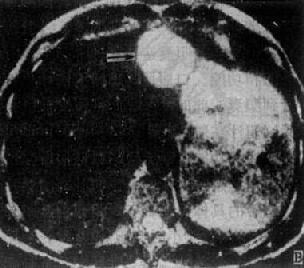

原发性肝癌

图4-3-5 原发性肝癌

CT增强扫描,肝右叶有一较大圆形低密度肿块(↓),其边缘

部可见多个较密度的强化结节,其强化程度不如正常肝,中

心部仍为未强化的低密度区